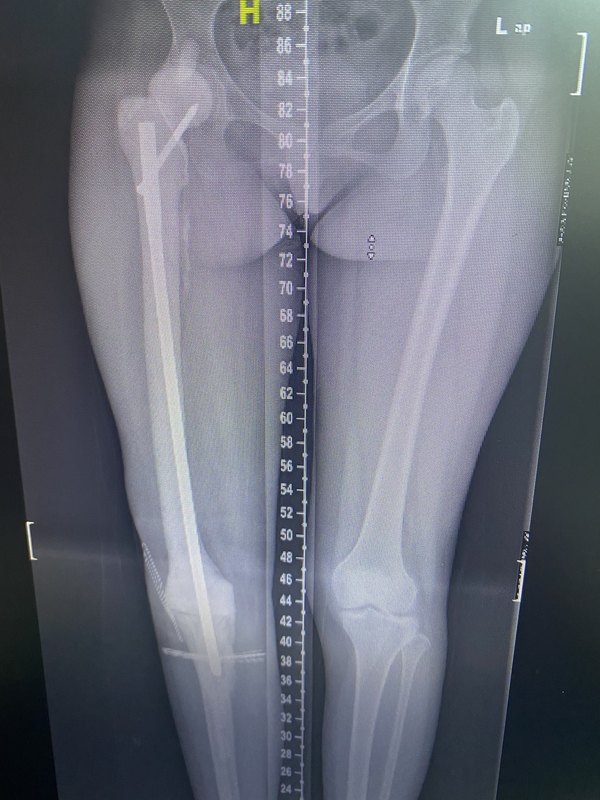

近年,隨著外科技術(shù)的提高,化療等綜合治療的實施,骨肉瘤的治愈率(5年生存率)在國內(nèi)目前穩(wěn)定在60-70%,對于原發(fā)初治,沒有轉(zhuǎn)移的兒童青少年骨肉瘤或尤文肉瘤來說,可以達(dá)到90%,腫瘤治好是最為重要的,但隨著骨骼發(fā)育期患兒長期生存,后續(xù)會出現(xiàn)肢體短縮等問題,也就是手術(shù)部位的骨骼無法繼續(xù)發(fā)育帶來的肢體短縮,雙下肢不等長這一問題。在門診這類患兒逐年增多,下面就簡單介紹一下在腫瘤期治療后,對于肢體不等長治療我們應(yīng)當(dāng)如何進(jìn)行決策和實施。首先,整體上要判斷患兒處于骨骼發(fā)育狀態(tài)還是接近或骨骼已經(jīng)發(fā)育結(jié)束,如果是前者仍要充分考慮到從就診時間往后的肢體進(jìn)一步短縮程度,如果已經(jīng)發(fā)育基本結(jié)束,則可以針對目前的短縮程度進(jìn)行糾正。下圖為整個兒童保肢治療關(guān)于不等長的預(yù)期和方法選擇,左邊黑白色灰度條,年齡越小,面臨的肢體不等長長度越大,治療難度越大,應(yīng)采用不同治療方法這樣避免遠(yuǎn)期出現(xiàn)無法糾正治療的問題。肢體不等長是兒童保肢術(shù)后最主要的遠(yuǎn)期并發(fā)癥,上肢的不等長一般對功能影響不大,但是下肢不等長會嚴(yán)重影響功能。股骨遠(yuǎn)端和脛骨近端是原發(fā)骨腫瘤好發(fā)部位,兩個部位骺板分別占下肢長度生長的35%和30%,此外還有一些其它因素影響肢體不等長程度,這些因素包括化療,鄰近關(guān)節(jié)骺板受累,肌肉喪失或萎縮,對側(cè)肌肉過度增生。肢體不等長的治療方法包括矯正鞋和外科治療,后者包括可延長假體,骨骺保留,對側(cè)骨骺損毀或骨延長。在制定治療計劃時,對于肢體不等長的預(yù)測十分重要,因為需要根據(jù)不等長程度選擇合適的治療方案。預(yù)測成年后身高常需要綜合多方面預(yù)測結(jié)果,如家庭成員身高,生長圖表等方法。對于超過5-8cm的肢體短縮一般需要肢體延長進(jìn)行糾正,最常用的治療方法是通過外固定架進(jìn)行骨延長,安全延長范圍是受累骨全長的15-25%。使用外架骨進(jìn)行骨延長常見的并發(fā)癥包括釘?shù)栏腥?,軟組織張力過高,關(guān)節(jié)脫位,肌肉反張,骨骺早閉,新生骨延遲愈合,鄰關(guān)節(jié)僵直,外架拆除后新生骨青枝骨折。小于2cm的肢體不等長不需要處理,患者一般沒有明顯的臨床癥狀和功能異常,這一范圍內(nèi)的不等長可以通過矯正鞋糾正,對于<1cm不等長可以通過正常鞋增加內(nèi)增高實現(xiàn),>1cm不等長需要在鞋跟處增高。2-5cm的不等長一般伴有步態(tài)異常,可以通過矯正鞋或?qū)?cè)骺阻滯進(jìn)行糾正,但骺阻滯需要在準(zhǔn)確的時間進(jìn)行,這樣可以避免矯正不夠或過早阻滯。一般情況下身高的65%來自下肢骨骼發(fā)育,股骨遠(yuǎn)端(39%)平均每年生長9mm,脛骨上端(28%),平均每年生長6mm。大于5cm的不等長一般需要手術(shù)治療。在這個范圍內(nèi)的肢體不等長,可以通過健側(cè)腿的生長調(diào)控減少不等長進(jìn)一步加重,最常用的方法是經(jīng)皮骺阻滯。對于>5-8cm的肢體短縮一般采用短縮側(cè)肢體延長的方法進(jìn)行糾正,最常用的延長方法是通過外固定架進(jìn)行,一般為單邊外架或環(huán)形圈架。延長過程一般將外固定架固定后進(jìn)行截骨,而后以每天1mm速度牽開,一般可以延長所在長骨的15-25%的長度。常見的并發(fā)癥包括釘?shù)阑騻诟腥?,軟組織張力過高,關(guān)節(jié)脫位,肌肉反張,骨骺早閉,延長骨延遲愈合,鄰關(guān)節(jié)僵直,外架相關(guān)機(jī)械并發(fā)癥,外架拆除后的新生骨疲勞骨折。一般需要定期復(fù)查降低一些并發(fā)癥的發(fā)生,釘?shù)乐車o(hù)理,外架調(diào)整和功能康復(fù)對于延長手術(shù)的成功和患者延長期間的生活質(zhì)量都十分重要。預(yù)計肢體不等長>18-20cm(需要>3次肢體延長)的患兒,較早的采用截肢或旋轉(zhuǎn)成型可能使患兒受益。對于骨延長來說,骨缺損由新生骨填補(bǔ),骨延長的基礎(chǔ)是骨折愈合過程中出現(xiàn)的功能性加速重構(gòu)和骨愈合。Ilizarov最先應(yīng)用該技術(shù),該技術(shù)主要是進(jìn)行皮質(zhì)骨切斷,保留骨外膜和髓內(nèi)結(jié)構(gòu)的連續(xù)性。延長一般在截骨后7-14天開始,每天一般可以延長1mm,但是一般需要新生骨達(dá)到負(fù)重強(qiáng)度需要兩倍于延長的時間。雖然文獻(xiàn)報道的每厘米延長時間從8.1天到95天不等,但一般延長估算時間為每厘米一個月。骨延長最常見的并發(fā)癥是釘?shù)栏腥荆潭ㄡ敂嗔?,新生骨骨折,鄰近關(guān)節(jié)脫位,皮膚內(nèi)陷,骨吸收,對線異常。骨骼生長預(yù)測在臨床治療中,由于切除腫瘤需要進(jìn)行骺板的切除,在手術(shù)計劃時需要考慮患者年齡,骨骺發(fā)育潛能,以及手術(shù)帶來的生長丟失,綜合考慮以上因素決定重建方式及后續(xù)的肢體不等長的解決方案,進(jìn)行系統(tǒng)性術(shù)前計劃,所以在兒童保肢手術(shù)治療制定術(shù)前計劃時,對于受累骺板生長潛能的預(yù)測十分重要。常用的方法包括Anderson’s生長潛能預(yù)測,Moseley’s生長曲線法和Paley’s系數(shù)表法,國內(nèi)一直缺乏我國兒童骨骼發(fā)育特點的流行病學(xué)數(shù)據(jù),并且惡性腫瘤患兒往往需要接受化療,或放療,這些治療因素對于骺板的生長也會產(chǎn)生一定影響。在臨床上經(jīng)常進(jìn)行粗略估算,即骺板發(fā)育結(jié)束的年齡分別是男孩16歲,女孩14歲;股骨近端、股骨遠(yuǎn)端、脛骨近端、脛骨遠(yuǎn)端分別占下肢發(fā)育的15%、35%、30%、20%;或者按股骨近端骺板、股骨遠(yuǎn)端骺板、脛骨近端骺板和脛骨遠(yuǎn)端骺板每年生長的長度分別為3mm、9mm、6mm和5mm。這些數(shù)據(jù)對于治療方案制定、可延長關(guān)節(jié)假體設(shè)計等都是重要的參考數(shù)據(jù)。目前也可以通過PaleyGrowthApp進(jìn)行生長潛能或肢體不等長預(yù)測。我們在臨床實踐中發(fā)現(xiàn),通過核醫(yī)學(xué)骨掃描方法,可以通過骺板濃聚程度判斷骺板生長潛能,有較好的預(yù)測作用。這可能作為由于外傷、感染等原因?qū)е瞒堪鍝p傷,進(jìn)行患者個體預(yù)測受累骺板生長潛能的有效方法。將病變骺板與健側(cè)同一位置骺板進(jìn)行感興趣區(qū)濃聚比較,進(jìn)行濃聚降低程度比值計算,定量骨骼發(fā)育受累程度,作為臨床患者個體某一特定潛在受累骺板生長潛能受影響程度的預(yù)測方法。對于一些已經(jīng)置換過關(guān)節(jié)的患者,需要根據(jù)之前人工關(guān)節(jié)的情況進(jìn)行評估,根據(jù)人工關(guān)節(jié)情況,骨質(zhì)條件,目前關(guān)節(jié)功能等多方面進(jìn)行評估,綜合制定方案。對于保肢治療后的肢體不等長治療,要通過詳細(xì)的評估,充分認(rèn)識當(dāng)前面臨的問題,準(zhǔn)確預(yù)估之后可能潛在的進(jìn)一步不等長程度,結(jié)合患者對治療期望等多種因素綜合制定治療方案,需要治療經(jīng)驗豐富,熟悉腫瘤治療及相關(guān)骨科技術(shù)(骨延長,人工關(guān)節(jié)等技術(shù))的醫(yī)院進(jìn)行治療。